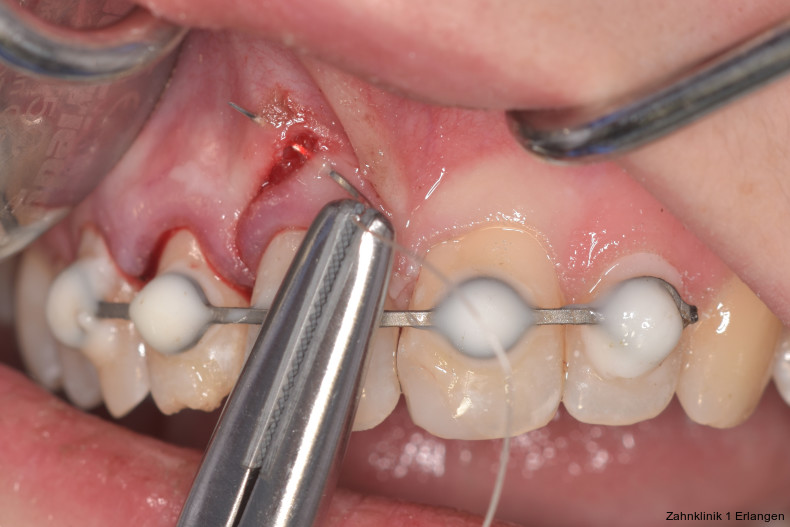

Bei Pulpaexposition ist die oberste Prämisse der Erhalt der Vitalität des Zahnes. Vor allem bei jungen Patienten und bei nicht abgeschlossenem Wurzelwachstum, aber auch bei erwachsenen Patienten ist die Vitalerhaltung die Methode der Wahl. Dabei spielen die Dauer und die Größe der Exposition keine wesentliche Rolle.10 Die oberste Gewebeschicht sollte zunächst im Sinne einer Mikropulpotomie angefrischt werden, was mit einem Diamantschleifer unter Wasserkühlung durchgeführt werden kann. Nach Blutstillung, zu der Natriumhypochlorit tropfenweise appliziert werden kann, wird das Sistieren der Blutung kontrolliert. Ist dies verifiziert, wird ein biokompatibles Material in direktem Kontakt mit dem Gewebe aufgebracht und der Zahn anschließend adhäsiv verschlossen.10 Dauert die Blutung an, beispielsweise weil der Unfall bereits mehr als 24 Stunden zurückliegt, kann tiefer pulpotomiert werden. Da eine traumatisch geschädigte Pulpa in der Regel vor dem Unfall gesund war, ist die Heilungskapazität meist sehr gut.11 Auch bei bestehender Exposition zur Mundhöhle hin über einen Zeitraum von Tagen kann die Pulpotomie noch hohe Erfolgsraten erzielen.

Tierexperimentelle Studien konnten zeigen, dass selbst bei über mehrere Tage hinweg freiliegender Pulpa Bakterien aus der Mundhöhle nicht tiefer als 2 mm in das Gewebe eindringen konnten.12 Kritisch ist dabei die erfolgreiche Blutstillung, die nach ca. fünf Minuten erreicht sein sollte. Die Erfolgsquoten der Pulpotomie nach Zahntrauma liegen deutlich über denen der direkten Überkappung bei über 90 Prozent. Dies ist auch in der revidierten Fassung der S2k-Leitlinie zum dentalen Trauma bleibender Zähne herausgestellt.3 Es ist zu beachten, dass bei begleitender Dislokationsverletzung die Durchblutung der Pulpa eingeschränkt oder sogar komplett unterbunden sein kann, was das Risiko des Misserfolges vitalerhaltender Maßnahmen signifikant erhöht.13 Daher sollte in solchen Fällen die Pulpektomie durchgeführt werden. Dies gilt ebenso bei umfangreichem Hartsubstanzverlust, wenn die definitive Restauration zusätzlich intrakanalär verankert werden muss.